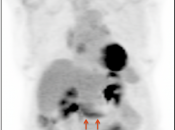

• The utility of PET/CT lies in its assessment of regional nodes and distant metastatic disease.

• Distant Disease: Most commonly to the liver, peritoneum, lung and bone.